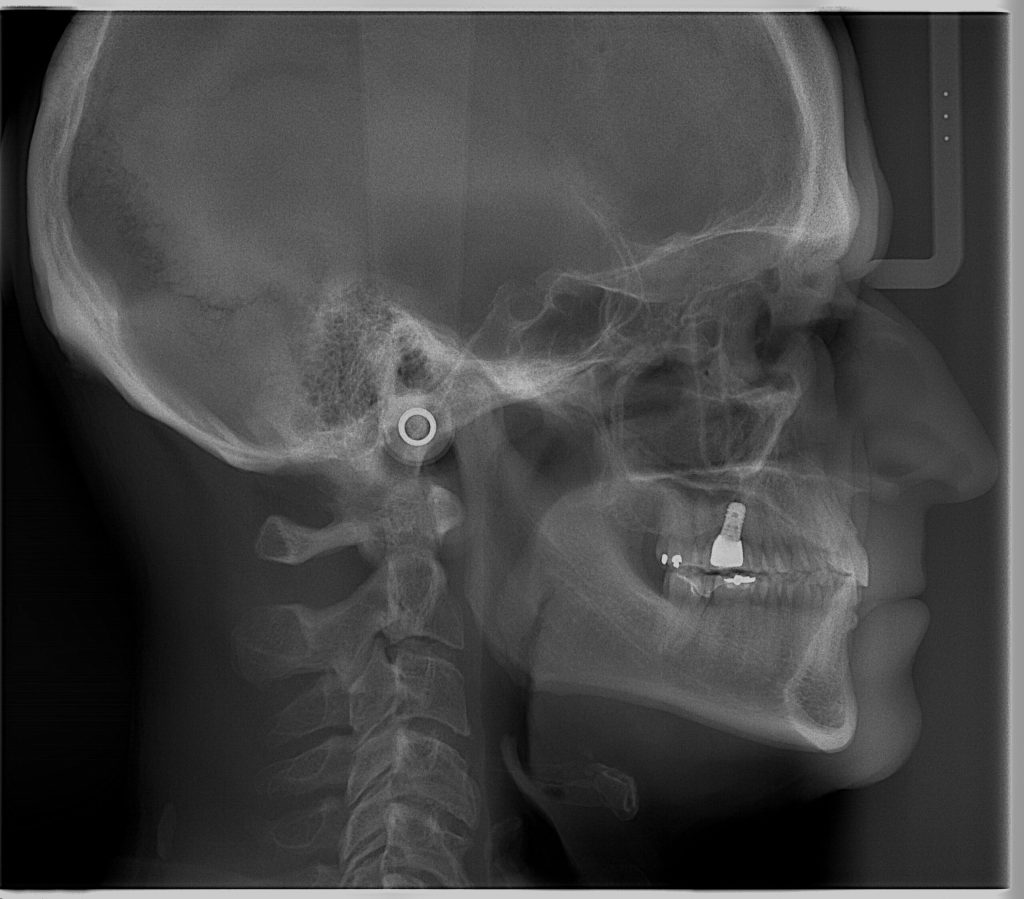

El Centro Radiológico Diagnóstico Oral 3D, es una empresa antioqueña que ofrece a sus pacientes desde el año 2009, tecnología de vanguardia en radiografías tridimensionales con calidad fotográfica. Las posibilidades para mejorar la eficacia en los diagnósticos bucales son evidentes, también lo son las posibilidades de manipulación de imagen. El sistema de imágenes en 3D ofrece detalles sin precedentes, convirtiéndola en la opción idónea para la mayoría de aplicaciones odontológicas, incluyendo implantes, tratamiento de conductos, ortodoncia, odontopediatría, periodoncia y cirugía

El mayor beneficiado con el uso de esta tecnología es el paciente, el cual podrá ser evaluado en todas sus dimensiones con una baja dosis de radiación, con un costo accesible y sin contaminar  el medio ambiente. Dependiendo de la necesidad del paciente, hay varios tipos de tomografías y los especialistas en el área odontológica hacen uso de ellas según su especialidad.

La radiología oral especializada es fundamental para una práctica dental integral, proporcionando información específica que influye en la toma de decisiones clínicas y mejora los resultados del tratamiento para los pacientes